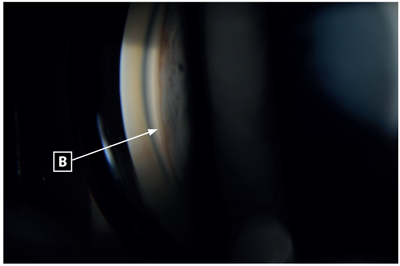

On examination, visual acuity was 6/96 in the right eye and 6/192 in the left eye. Intraocular pressures measured 11mmHg in the right eye and 40mmHg in the left. The left eye was injected, with a mid-dilated, non-reactive pupil and the cornea was cloudy. The anterior chamber appeared shallow in both eyes and there was cataract present in both eyes (nuclear sclerosis) (Figure 1). Gonioscopy revealed no visible angle structures in both eyes (Shaffer grade 0), with the left eye demonstrating extensive peripheral anterior synechiae and the right eye demonstrating appositional closure (Figures 2 and 3). There was no evidence of neovascularisation of the anterior segment.

Figures 2 and 3: Gonioscopy revealed no visible angle structures in both eyes (Shaffer grade 0), the left eye demonstrating extensive peripheral anterior synechiae and the right eye demonstrating appositional closure. A: pigment above Schwalbe’s line from previous appositional closure, now synechial closure in left eye. B: indentation gonioscopy of right eye demonstrating angle opening to reveal trabecular meshwork.